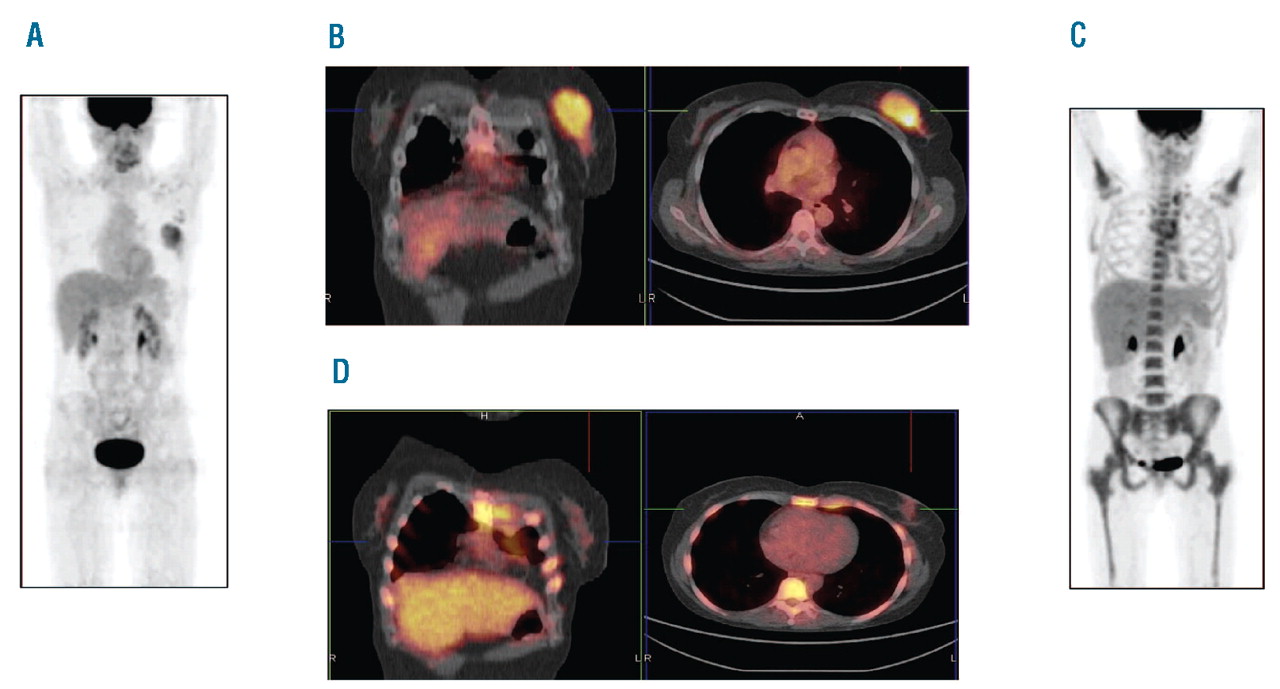

18FFDGPET/CT for detection of extramedullary acute myeloid leukemia

FDGPET MIP images of a 38yearold male with acute lymphoblastic Pet Ct Scan For Leukemia Cancer cells consume more of the tracer than do healthy cells, making them show up. This test can show if any. A ct scan of the chest or abdomen can help detect an enlarged lymph node or cancers in the liver, pancreas, lungs, bones and spleen. During a pet scan, a tracer (liquid that contains a small amount of radiation). Pet Ct Scan For Leukemia.